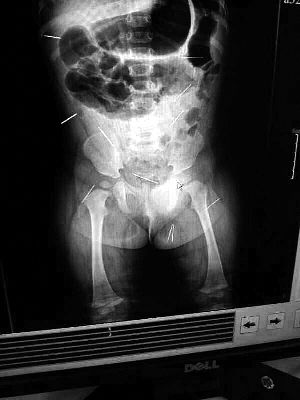

山東聊城11個月女嬰萱萱(化名)疑似被人以12根鋼針插滿臀部、腹腔等部位,昨天在兒童醫(yī)院會診后,醫(yī)生稱3根針靠近胸腔最危險,首批先行取出,預(yù)計將在下周二手術(shù)。孩子父母稱孩子一直由家人照顧,自家與他人并無冤怨。山東警方表示正在偵破中,不便透露案情。

“要不是當(dāng)初那幾個紅點(diǎn),可能到現(xiàn)在我們還不知道孩子身體里有鋼針!”昨天,在兒童醫(yī)院住院處,萱萱爸爸范先生稱,日前原本很愛笑的萱萱突然變得有些焦躁,一抱起來就哭,孩子母親偶然間在萱萱屁股上發(fā)現(xiàn)了幾個小紅點(diǎn)兒,原以為是蚊蟲叮咬,就醫(yī)結(jié)果卻讓人不寒而栗?!搬t(yī)院拍出的片子上,萱萱的體內(nèi)有12根鋼針,插滿臀部、腹腔、骨盆等各個部位?!狈断壬榻B,因?yàn)殇撫樢焉钊塍w內(nèi),要是孩子不哭鬧,他們很難發(fā)現(xiàn)。

北京晨報記者了解到,目前體內(nèi)的12根鋼針多分布在孩子的臀部,一根在腹部,其余3根在胸腔附近,其中一根很接近心臟?!耙?yàn)楹⒆犹?,醫(yī)生們害怕取針的時候?qū)λ斐蓚?,在胸腔附近?針可能會威脅她的生命”。